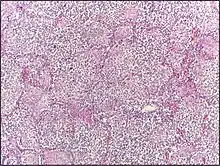

![]() | Reactive hyperplasia of lymph node | Histopathology of a reactive lymph node by the cystic duct in a case of cholecystitis. | Category: Reactive hyperplasia of lymph node | Reactive hyperplasia |